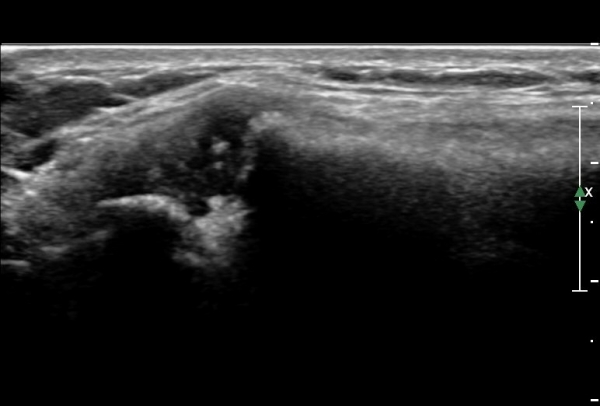

ÁÂÃø Èä°ñ¼â°ñ°üÀýÃÊÀ½ÆÄ°Ë»ç¿¡¼­ ƯÀÌ ¼Ò°ßÀ» º¸ÀÌÁö ¾ÊÀ½(»çÁø 1, 2).

¿ìÃø Èä°ñ¼â°ñ°üÀýÃÊÀ½ÆÄ°Ë»ç¿¡¼­ °üÀýÀÇ ÅðÇ༭ º¯È­°¡ °üÂûµÊ(»çÁø 3, 4).